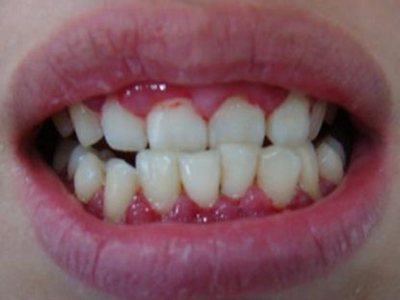

慢性龈炎又称边缘性龈炎或单纯性龈炎,主要表现为游离龈和龈乳头因炎性水肿,而变为鲜红或暗红色,龈缘变厚,龈乳头圆钝肥大。慢性龈炎的患病率高,治愈后仍可复发,部分患者可发展成为牙周炎。

慢性龈炎的病损部位一般局限于游离龈和龈乳头,以前牙区为主,尤其以下前牙区最为显著,患者常因刷牙或咬硬物时牙龈出血而就诊。游离龈和龈乳头颜色变为鲜红或暗红色,病变较重时炎性充血可波及附着龈。龈缘变厚,龈乳头圆钝肥大,可增生呈球状,覆盖牙面。牙龈松软脆弱,缺乏弹性。

龈缘附近牙面上堆积的牙菌斑是引起慢性龈炎的始动因子,其他如牙石、食物嵌塞、不良修复体等均可促使牙菌斑积聚,引发或加重牙龈炎症。